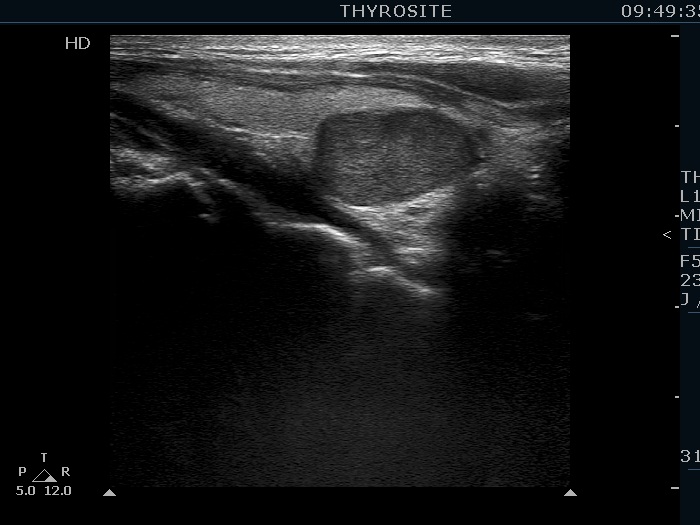

Clinical data: A 43-year-old woman was diagnosed with primary hyperparathyroidism. Scintigraphy disclosed an enlarged right lower parathyroid. The initial cause of evaluation was elevated serum calcium level detected by chance. The patient was referred in order to confirm and to accurately localize the lesion before surgery.

Ultrasonography. The thyroid was echonormal. There was a hypoechoic mass within the lower pole of the right lobe. The lesion was surrounded by thyroid tissue throughout.